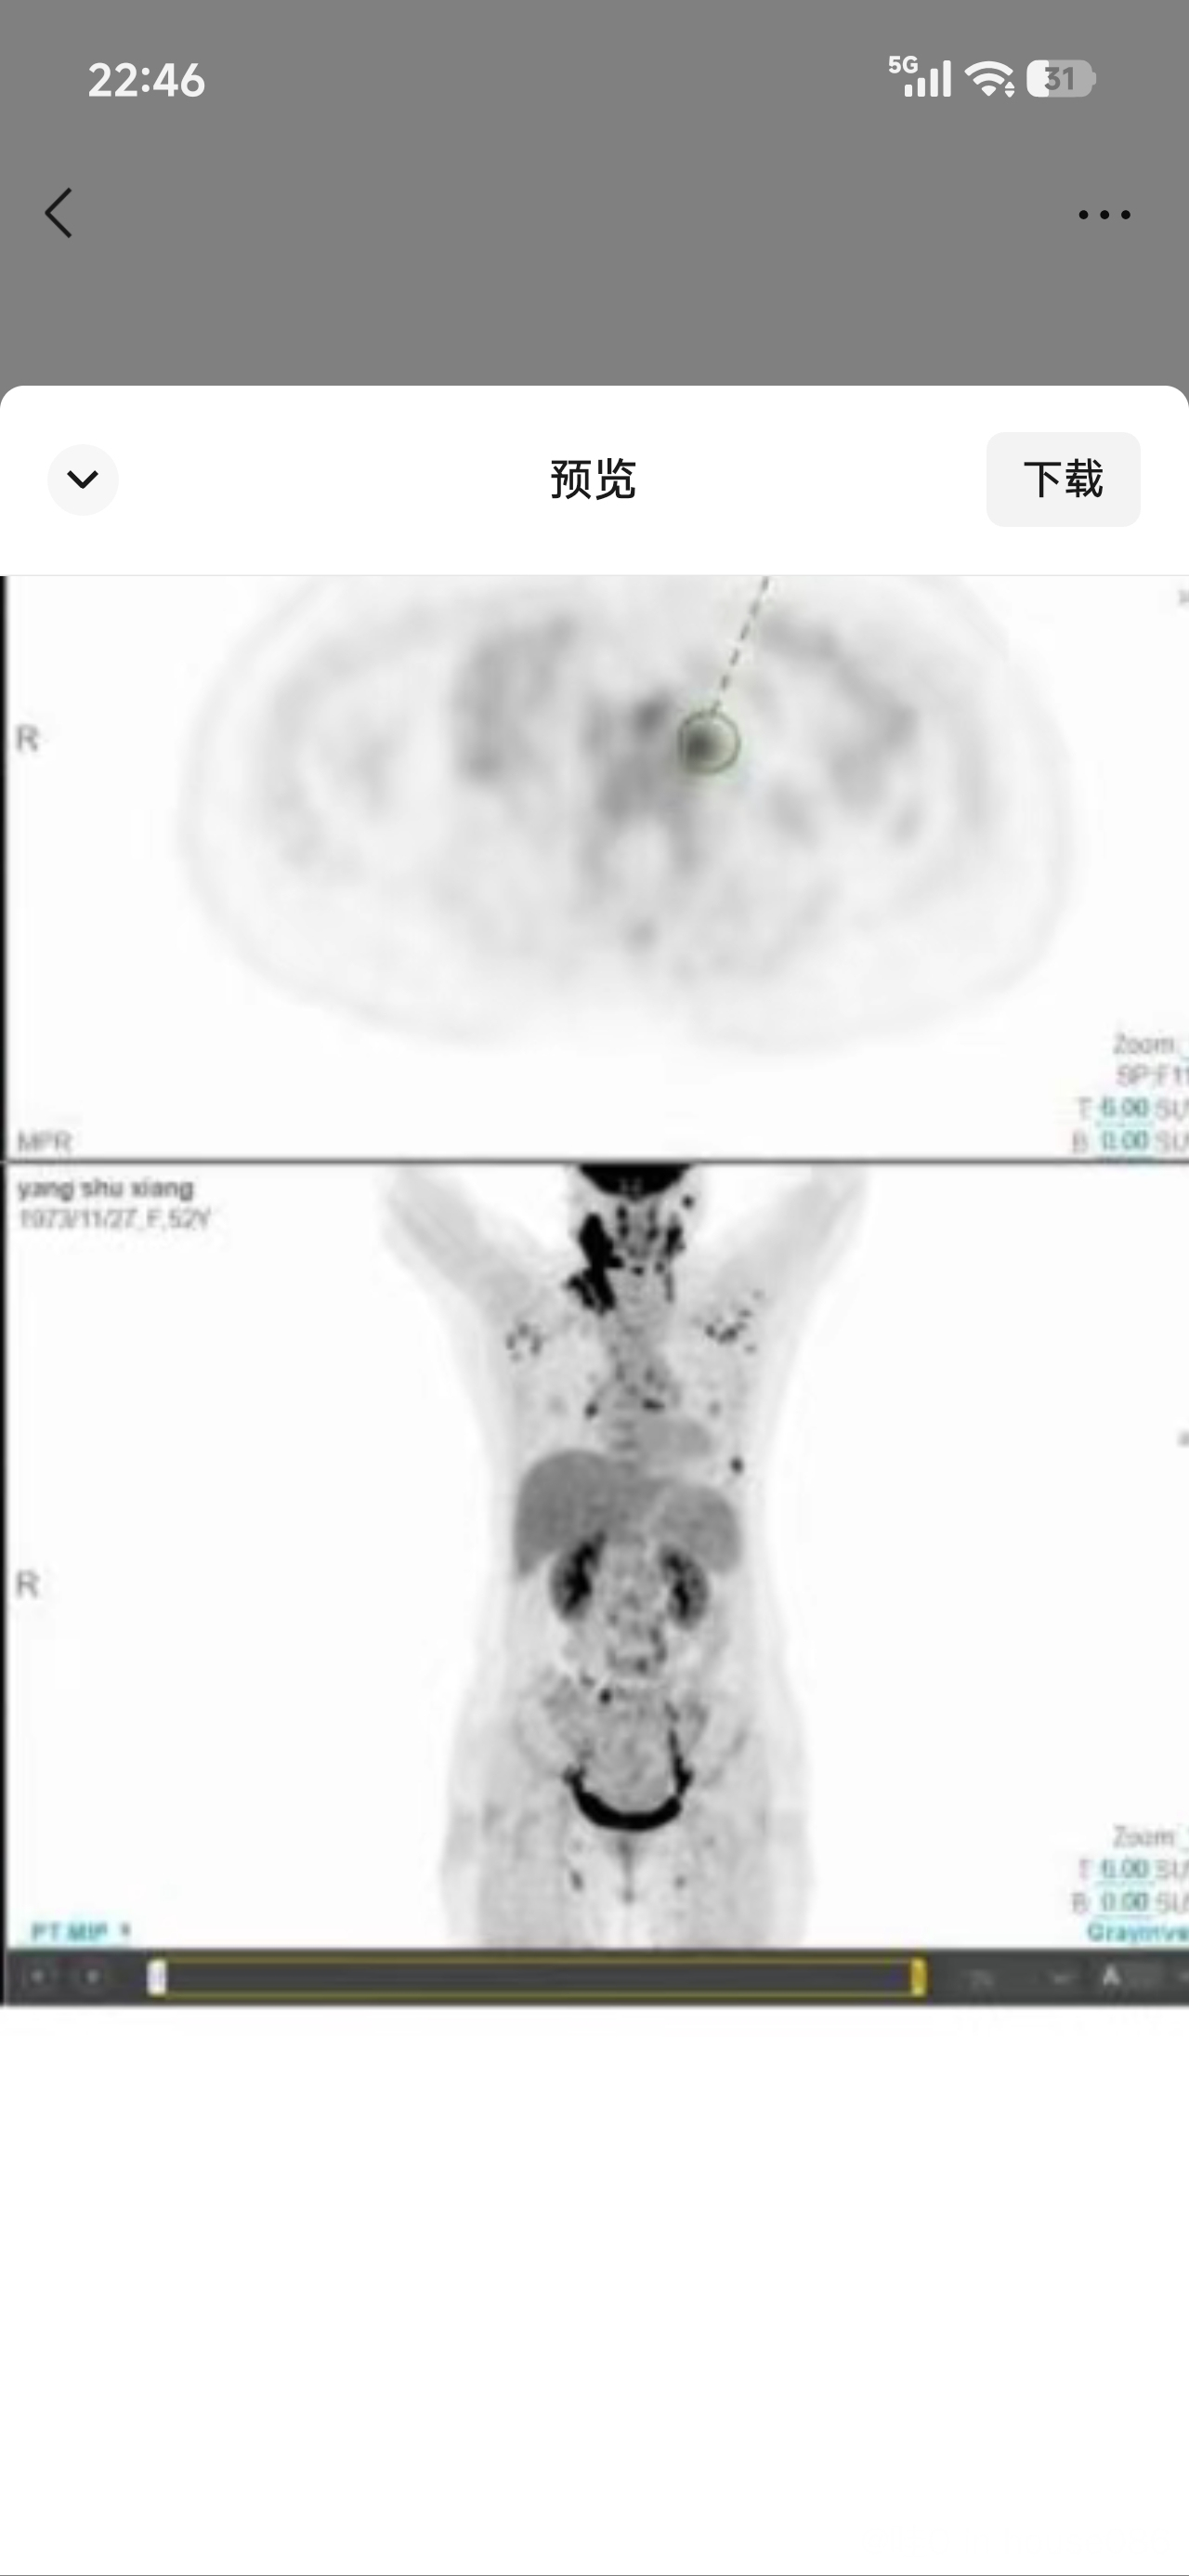

从代谢看,那个SUVmax 22的应该高度怀疑,而且PET医生已经给了明确提示了,他用的描述是“符合淋巴瘤”,“符合”这是确定性高的描述

但要确证一定要活检,病理才是唯一金标准。赶快去做吧,没有有了病理才能知道是具体什么分类,分型,才能制定治疗方案。 |